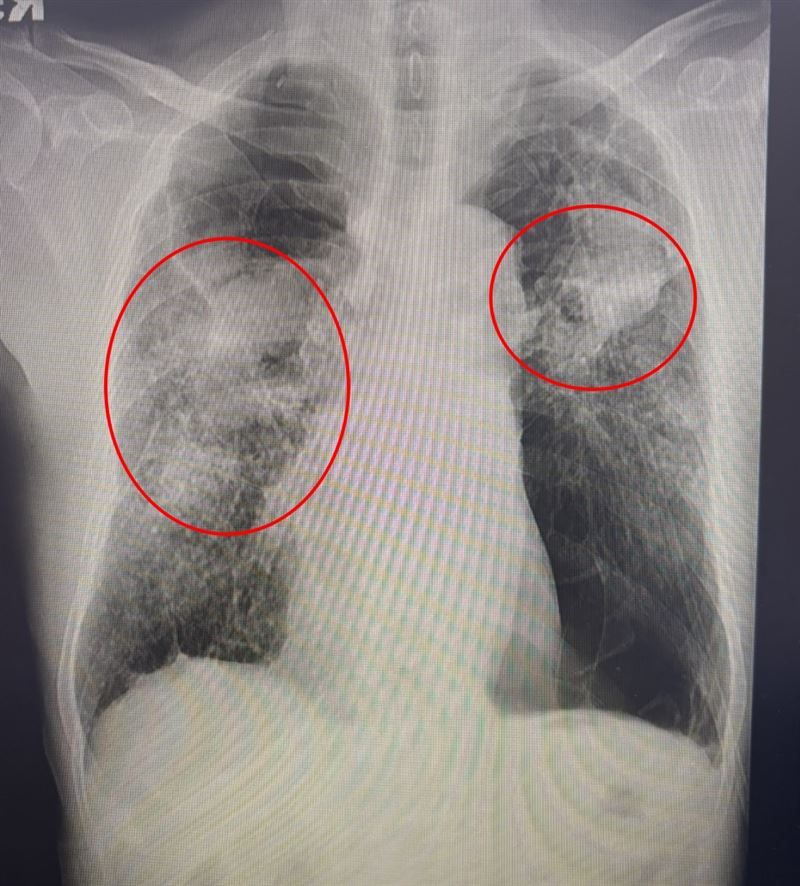

一名70多歲老翁,長年有慢性阻塞性肺病及心律不整,日前突然發高燒,甚至喘到連走幾步路都困難,家屬緊急將他送醫,經胸腔內科醫師檢查,確診為A型流感併發出肺炎,胸部X光片顯示肺部呈現一大片白霧,呼吸功能急遽惡化,立即安排住院治療,雖然積極投藥治療,但因併發症多,恢復相當緩慢,住院兩周才出院。

光田綜合醫院胸腔內科簡格凌醫師指出,患者因慢性阻塞性肺病導致原本肺功能就差,加上感染A型流感,導致呼吸道症狀嚴重,需要依靠氧氣面罩維持呼吸。雖然積極投予抗病毒藥物與抗生素,但因患者出現多項併發症,導致病程延長,一般流感患者約一周出院,老翁卻整整住院兩周病情才穩定出院。醫師表示,「這就是典型的流感重症案例,若再晚送醫,後果不堪設想。」。